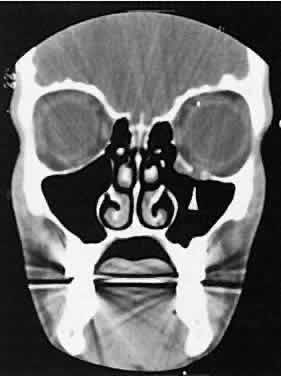

Dermoid cysts are located most frequently in the superior temporal quadrant of the orbit. They may be located anywhere within the orbital confines. Lesions in the lacrimal fossa or along the posterior lateral wall may communicate intracranially or into the temporalis fossa. Radiographically, the cysts are well-delineated and have lucent interiors with CT attenuation densities in the fat range (Fig. 19). Calcification along the rim of the cyst may be present. The bony changes have irregular, notched borders rather than the moth-eaten appearance associated with malignancy. The range of CT appearances can be quite wide.67

Fig. 19. Axial (A) and coronal (B) scans of a dermoid cyst. Note the low attenuation (lower than retrobulbar fat) within the well-demarcated cyst located in the right lacrimal gland fossa.